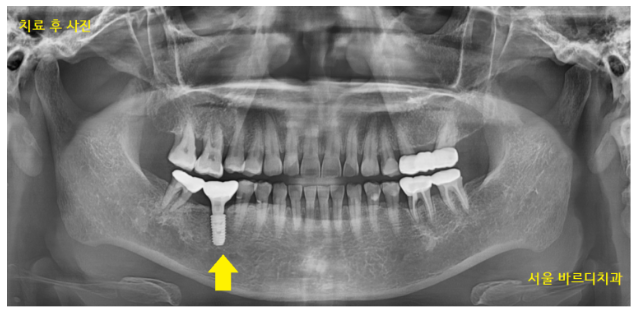

240328

보철 머리를 만들어드린 사진입니다.

전신질환이 많으셨지만

협진 진료

수술 후 충분한 휴식으로 컨디션 관리를 해드렸더니

치료 마무리까지 무사히 끝낼 수 있었습니다.